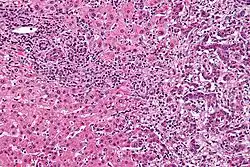

Vermutlich durchläuft das Gallengangskarzinom – ähnlich wie der Dickdarmkrebs – eine Serie von Entwicklungsschritten von Hypoplasien über Metaplasien und Dysplasien hin zum Karzinom (Adenom-Karzinom-Sequenz).[31] Deshalb spielen Prozesse wie chronische Entzündungen und eine Verengung der Gallenwege, die mit einer Flussbehinderung der Gallenflüssigkeit einhergehen, bei der Entwicklung dieses Tumors eine Rolle.[31][32][33] Das histologische Bild des Gallengangskarzinoms kann von undifferenziertem bis hin zu gut differenziertem Gewebe variieren. Der Tumor ist oft von einem fibrotischen oder desmoplastischen Gewebe umgeben. Im Falle einer ausgeprägten Fibrose kann es schwierig sein, ein gut differenziertes Karzinom der Gallengänge von einem nur reaktiv veränderten Epithel zu unterscheiden. Es gibt keine völlig spezifische immunhistochemische Färbung, die bösartig verändertes von gutartigem Gallengangsgewebe unterscheidet. Markierungen für Cytokeratin, Carcinoembryonales Antigen und Mucine können bei der Diagnose hilfreich sein.[34] Die meisten Tumoren (über 90 %) sind Adenokarzinome.[35]

Pathologie

Gallengangskarzinome gehören zu den Adenokarzinomen und sind gewöhnlich histologisch gut bis mäßig differenziert. Eine Immunhistochemie ist bei der Diagnose hilfreich, wenn ein differenziertes Gallengangskarzinom von Metastasen anderer gastrointestinaler Tumoren unterschieden werden soll.[55] Gewebeabstriche sind selten diagnostisch aussagekräftig.[56]